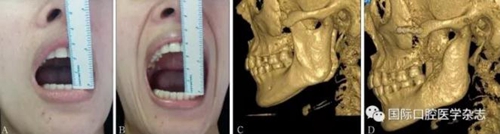

A:術(shù)前開口度;B:術(shù)后開口度;C:術(shù)前影像學(xué)檢查片;D:術(shù)后影像學(xué)檢查片。

圖 18 關(guān)節(jié)盤復(fù)位錨固術(shù)前后對比

圖 19 關(guān)節(jié)成形術(shù)前后對比

圖 20 顴弓骨折修復(fù)術(shù)前后對比